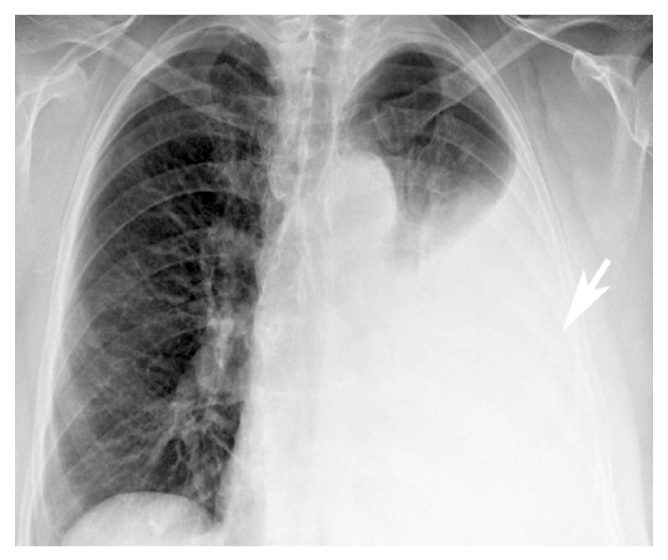

Результаты физикального, лабораторного и инструментального исследований. При первичном осмотре тахипноэ (частота дыхательных движений 39 в минуту), тахикардия (частота сердечных сокращений 115 в минуту), артериальное давление 110/70 мм рт.ст., насыщение крови кислородом (SpO2) 93%. Показатели общего и биохимического анализа крови в пределах референсных значений. При рентгенографии органов грудной клетки состояние после резекции I–II сегментов левого лёгкого, признаки массивного спонтанного пневмоторакса справа (рис. 3).

Рис. 3. Пациентка А., 53 года. Рентгенограмма грудной полости. Спонтанный пневмоторакс справа, коллабированное правое лёгкое (стрелка).